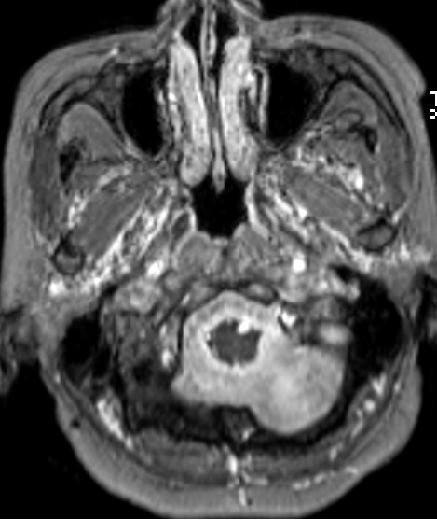

2015-4-1 MRI

2015-4-1

2015-4-3